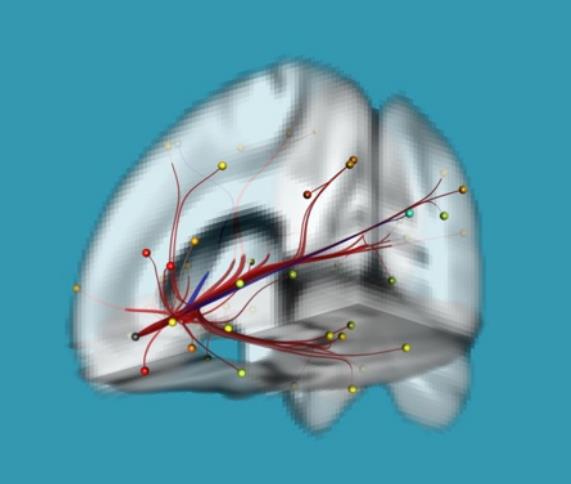

«Изменения коннектома головного мозга у пациентов с детским церебральным параличом в поздней резидуальной стадии при транслингвальной нейростимуляции». Обобщена МР-семиотика структурных и функциональных изменений головного мозга у детей со спастической диплегией. У детей с ДЦП в поздней резидуальной стадии преобладает снижение коннективности между компонентами сети выявления значимости и корой лобно-теменной области, компоненты которой также структурно связаны с компонентами сенсомоторной сети. При выполнении коннектометрического анализа трактов после ТЛНС (основная группа) выявлено повышение фракционной анизотропии более чем на 20 % (p < 0,001) в передней спайке (47 % от общего количества волокон), правом нижнем лобно-затылочном пучке (13 % волокон), левой поясной извилине (10 % волокон), правой зрительной лучистости (6,7 % волокон), мозолистом теле (6 % волокон), правой поясной извилине (1,3 %) (рисунок).

|

|

|

| Графическое представление результатов межгруппового статистического анализа: 2D-реконструкция проводящих путей белого вещества головного мозга с повышением ФА после ТЛНС в аксиальной (а), сагиттальной (б) и корональной (в) плоскостях. Показаны проводящие пути и часть их волокон, которые повысили ФА более чем на 20 % после комплексной реабилитации | ||

При выполнении коннектометрического анализа трактов после стандартной двигательной реабилитации (группа сравнении) статистически значимого повышения фракционной анизотропии (более чем на 20 %) не выявлено. При проведении диффузионной МРТ у детей с ДЦП в поздней резидуальной стадии выявлено статистически значимое снижение фракционной анизотропии в трактах белого вещества головного мозга, что свидетельствует о нарушении общих процессов миелинизации и, следовательно, скорости проведения нервных импульсов по их аксонам. Выявлены структурные и функциональные изменения головного мозга у пациентов с ДЦП после ТЛНС, которые свидетельствуют об усилении активации процессов нейропластичности.